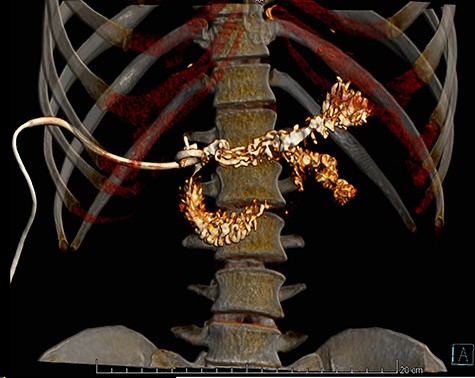

A fistulogram using the catheter was completed, which confirmed our diagnosis. As the patient remained in good condition and asymptomatic, the duodenal perforation was considered contained and conservative management was decided (Fig. 3). Total parental nutrition and NPO (nil per os) were started and the output of the drain dramatically diminished. On the 10th after the diagnosis, the catheter was removed without complications, as the daily output of the drainage did not exceed 50 cc. Sips of clear liquids were initiated immediately, followed by a full diet with no difficulties. He remained completely asymptomatic and was discharged on his 15th day. On follow-up consultations 3 months after the drainage procedure, patient is doing well.

CT reconstruction, the contrast is spreading to the duodenum and small bowel without leaks.